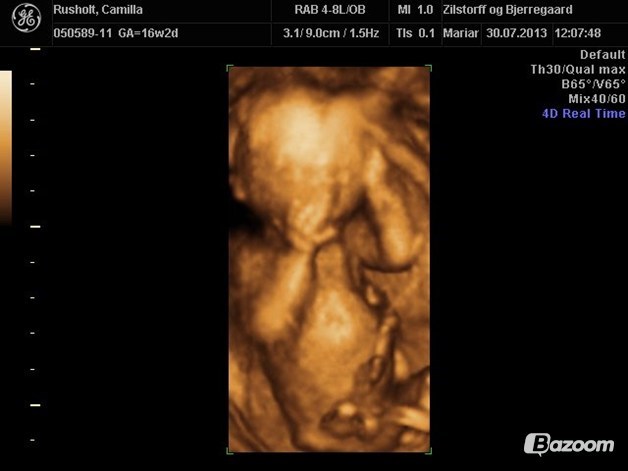

vi var til kønsscanning 14+2 hvor der også blev vist lidt 3D

Vedhæftede fotos (klik for at se i fuld størrelse)